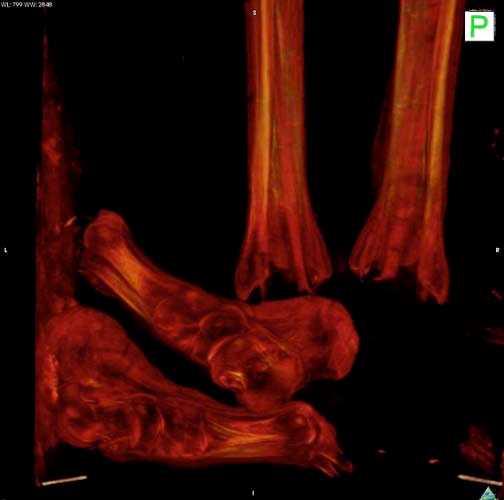

2. Fotoğrafta gördüğünüz Mısır mumyasının CT taraması, uygarlığının gizemlerini çözmeye yardımcı olacak.

Fotoğrafta gördüğünüz Mısır mumyasının CT taraması, uygarlığının gizemlerini çözmeye yardımcı olacak.

5. Yapılan taramalar M.Ö. 900 civarında Mısırlıların sağlığı ve davranışları konusunda önemli ipuçları verdi.

Yapılan taramalar M.Ö. 900 civarında Mısırlıların sağlığı ve davranışları konusunda önemli ipuçları verdi.